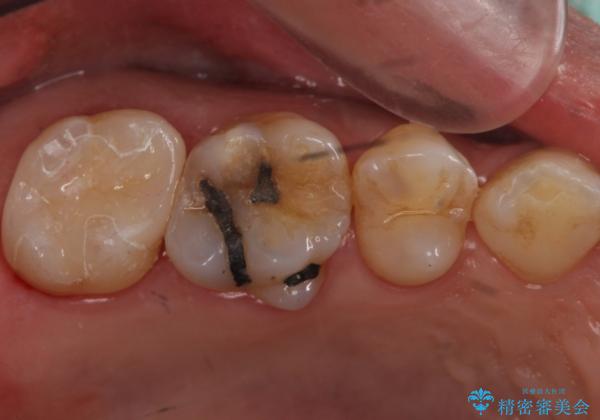

- 昔、治療された銀歯が気にな流ということを主訴で来院された患者様です。

銀歯を外し、虫歯治療を行い、セラミックインレーにて治療しました。

銀歯を除去し、虫歯をとって、セラミックインレーにて治療を行いました。